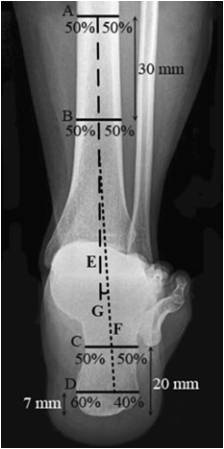

| Saltzman 位 1. 确定胫骨长轴E 2. 确定跟骨长轴F – 距跟骨最低处7mm处做水平线C,分为3:2 – 距跟骨最低处20mm处做水平线D:分为1:1 – 正常足:0°~5° – 外翻足:5°~10° – 严重外翻足:>10° – 内翻足:0°~-10° – 严重内翻足:<-10°   |

|

| 后足长轴位 1. 确定胫骨长轴E 2. 确定跟骨长轴F – 距跟骨最低处7mm处做水平线C,分为3:2 – 距跟骨最低处30mm处做水平线D:分为1:1   |